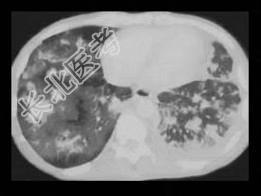

- 单项选择题男,27岁, 干咳,呼吸困难半月余, 有艾滋病病史半年余,请结合CT检查, 选出最可能的诊断 ( )

A、粟粒型肺结核

B、弥漫型肺癌

C、间质性肺炎

D、矽肺

E、Kaposi肉瘤